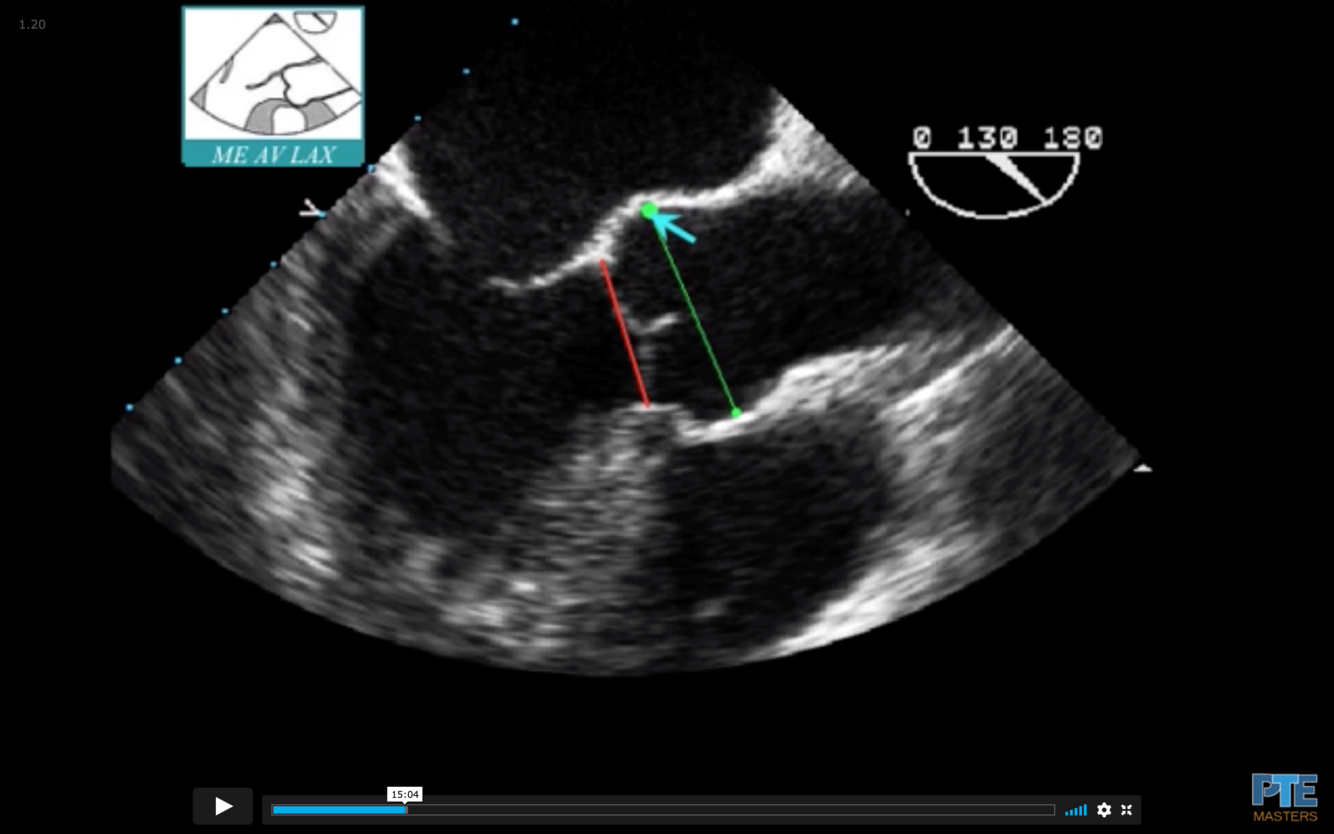

What is the measurement seen here?

Sinus of Valsalva

What is the blue arrow indicating?

Sinotubular Ridge or Sinuotubular Junction

What is seen in red?

Aortic Annulus